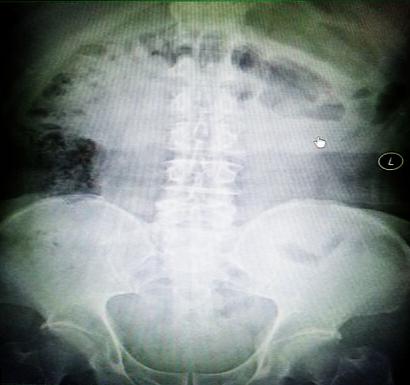

受試患者在結(jié)腸端端吻合術(shù)中,使用我司新研制產(chǎn)品達到了理想的預(yù)期效果?;颊咝g(shù)后7天、14X光片顯影,可降解腸道支架均能按研制設(shè)計的預(yù)期時間節(jié)點保持應(yīng)有強度,術(shù)后21X光片顯示可降解腸道支架已完全破碎,并排出體外。在整個試驗過程中,病患無任何不良反映,耐受良好。